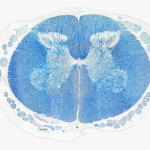

Know your spinal cord – Anterior spinal artery syndrome

Today we hit the three week mark in knowing your spinal cord! I’m hoping we can do a full four weeks, that would be quite the collection of knowledge. For those of you just joining in, you can find all of our posts in the neuroanatomy category ordered in reverse chronological order. As per the last few posts, we’ve covered the majority of the anatomy and now we are looking at different disorders of the spinal cord. Today we’re going to cover another type of injury, this one called anterior spinal artery syndrome, so let’s get started!